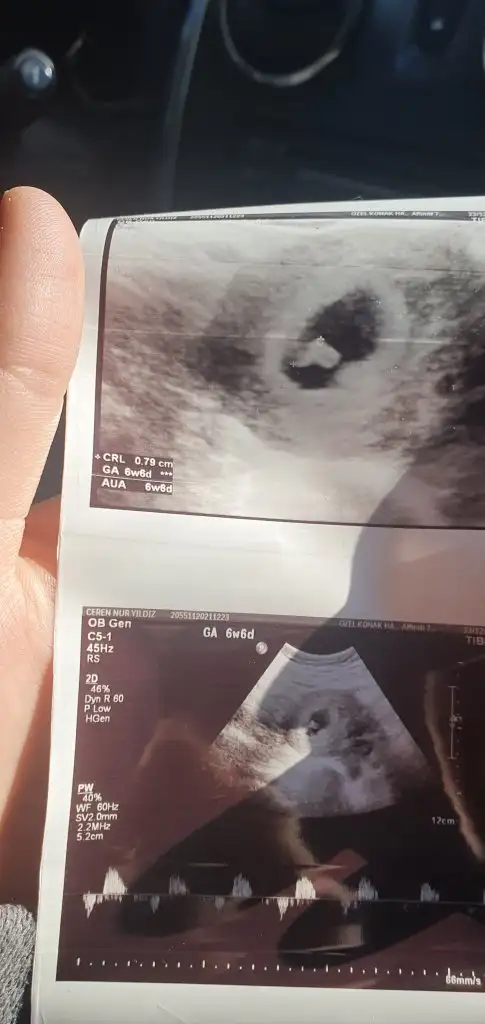

Canım benimkini yorumlar misin sat a gore 7+4 bu fotoda ama 9 haftalik cikti olcume gore ne sağ da ne sol da yorumalyamadim ben

Cok tesekkur ederim 6+4 haftalik olan bu daha saglikli bir bilgi olursa diye onu da yolluyorum cok oldum amaŞimdilik erkek yönünde ama en iyi 11 12 13 haftalar